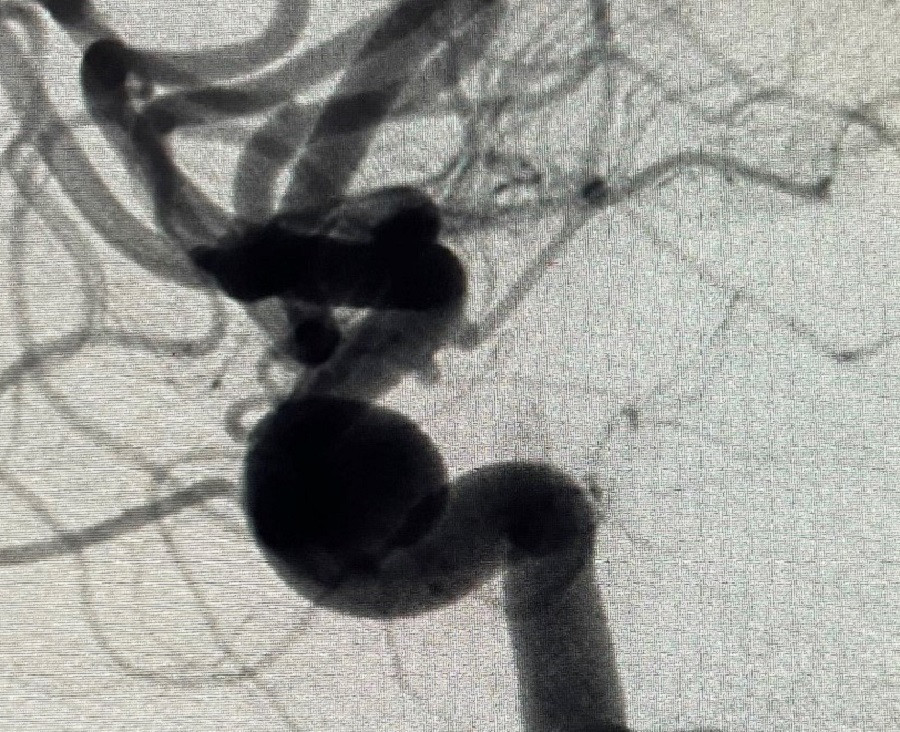

| Túi phình lớn ở mạch máu não dọa vỡ là nguyên nhân khiến người bệnh bị đau đầu dữ dội |

Theo BS. Phạm Định Chương, khoa Nội Thần kinh, người trực tiếp điều trị và can thiệp cho trường hợp trên, đây là bệnh nhân bị túi phình mạch não có kích thước lớn, nguy cơ vỡ túi phình cao. Do đó, việc điều trị để loại bỏ túi phình là ưu tiên quan trọng hàng đầu. Tuy nhiên, túi phình kích thước lớn, không thể điều trị bằng phương pháp thông thường như thả coil (nút túi phình mạch não bằng vòng xoắn kim loại) hay phẫu thuật. "Sau hội chẩn, chúng tôi đã quyết định can thiệp cho bệnh nhân bằng phương pháp đặt stent thay đổi dòng chảy”, BS. Chương cho hay.

Ê kíp bác sĩ đã tiến hành đặt stent, hướng dòng chảy theo chiều mạch máu, ngăn chặn thành công không cho dòng máu đổ vào túi phình. Phương pháp trên giúp túi phình mạch máu ngày càng teo nhỏ, vùng cổ túi phình sẽ từng bước nội mạc hóa, liền với mạch máu. Sau can thiệp, sức khỏe bệnh nhân đã bình phục tốt.